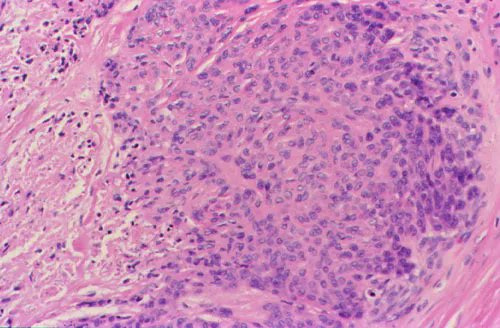

1/3. Rare Dan Tweetorial or Renal: Kidney Biopsy in young man with metastatic disease. Looks nasty! CA9, P63 and GATA 3 negative.

Daniel Berney (@daniel_berney) 's Twitter Profile Photo

As mentioned by many, this is Cystic trophoblastic tumour in a post chemo orchidectomy specimen. Degenerate remnants of choriocarcinoma after systemic chemo. hCG should only be mildly raised. As mentioned by Andres Martin Acosta (Andy): these tumours should be treated conservatively.